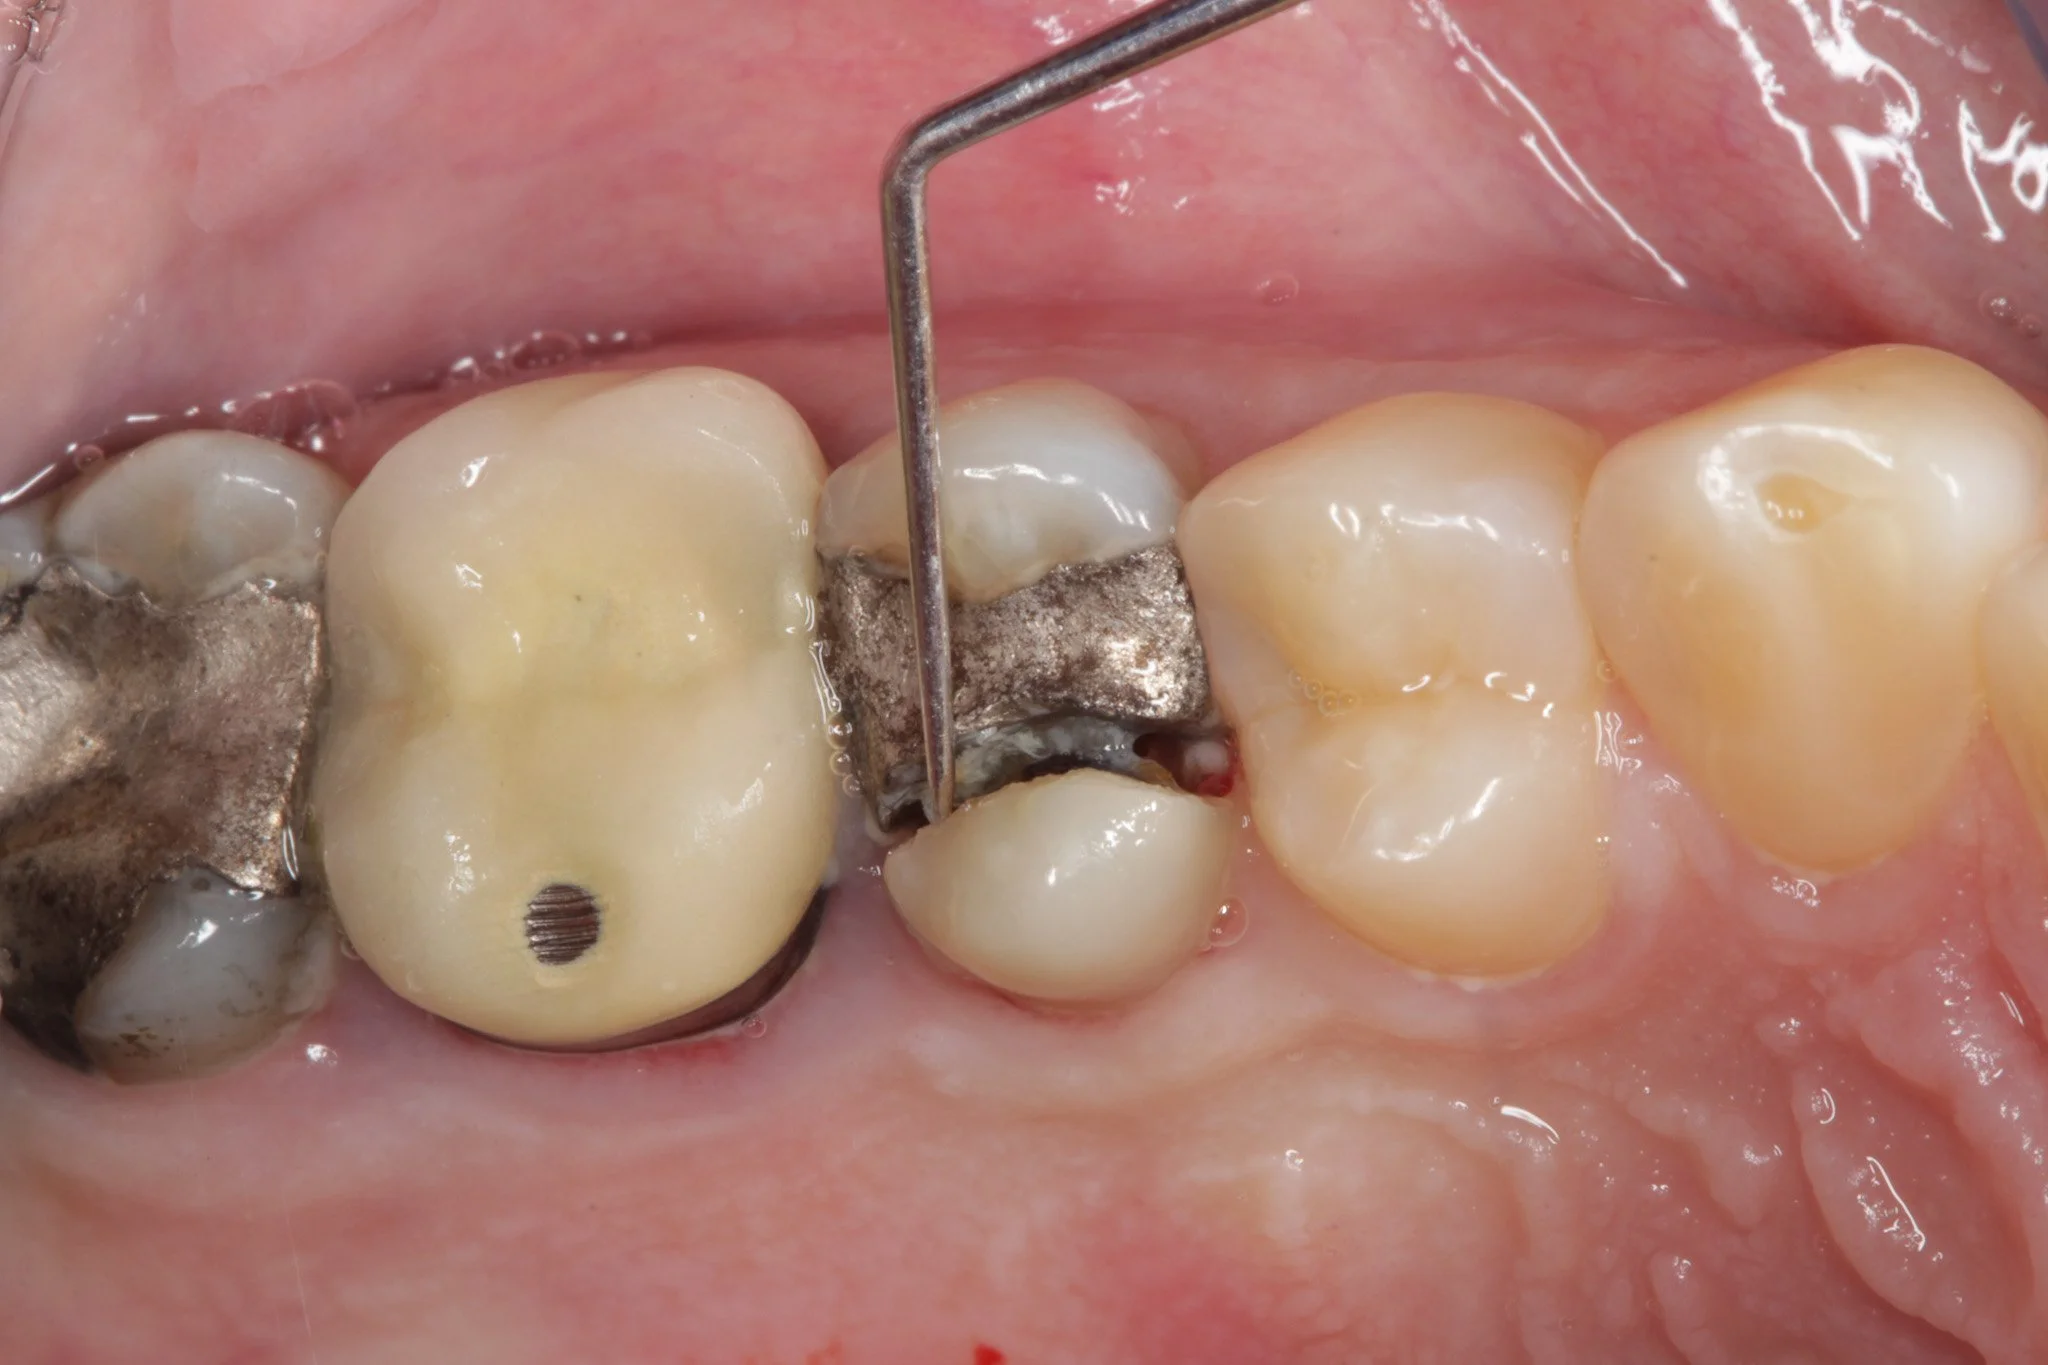

① 汚れがたまりやすく、むし歯・歯周病になりやすい

歯が重なっていたり、デコボコしていると、歯ブラシが届きにくい部分が増えます。

その結果…

- プラーク(細菌のかたまり)が残りやすい

- むし歯になりやすい

- 歯周病が進行しやすい

特に歯周病は、歯を支えている骨(歯槽骨)を溶かす病気です。

骨が減れば、歯はグラつき、最終的には抜歯になることもあります。